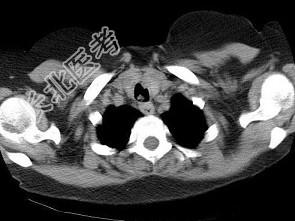

- 单项选择题男,68岁, 呼吸困难、轻度吞咽困难3月余,结合CT图像, 最可能的诊断是 ( )

A、气管乳头状瘤

B、气管脓肿

C、气管炎性假瘤

D、食管癌

E、甲状腺癌